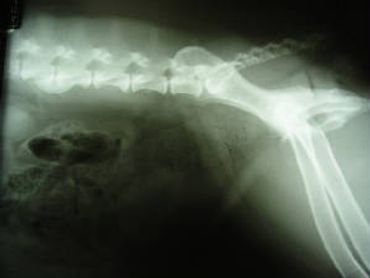

The spinal column is made up of four major vertebral regions: cervical (neck), thoracic (mid back), lumbar (low back) and sacral (pelvic). Dogs have seven cervical, thirteen thoracic, seven lumbar and three sacral vertebrae. There are also variable numbers of coccygeal or tail vertebrae. Intervertebral disks are located between the vertebral bodies starting at the second and third cervical vertebrae (C2-3) and extending to the seventh lumbar and first sacral vertebrae (L7-S1). The three sacral vertebrae are fused and therefore do not have disks. Intervertebral disks are present between the coccygeal vertebra as well, but are of little clinical significance.

The canine spinal anatomy is very similar to us humans, with the exception of 1 additional thoracic vertebra and 2 additional lumbar vertebra...